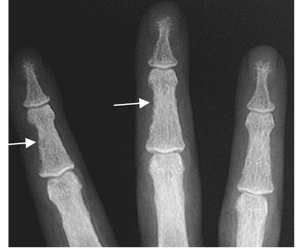

Tiene predominio por las manos y se caracteriza por osteopenia, reabsorción subperiostica en el aspecto radial de las falanges media y proximal del 2º y 3º dedos, aspecto en sal y pimienta del cráneo, reabsorción de los extremos distal de las clavículas y calcificación en los tejidos blandos. (3). (Fig 200).

Fig 200. Hiperparatiroidismo.

Rx AP. Reabsorción de los penachos en las falanges distales y de la zona lateral, en la falange media del 2º y 3º dedos.